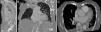

Following admission, hip replacement surgery was undertaken on day 3 of hospital stay, with no relevant complications. During routine early post-surgical observation in the intensive care unit, she was found to be hypoxic when sitting for the first time after the intervention. Physical examination was unremarkable, but interestingly the observed breathlessness and desaturation improved after lying flat and were reproducible on subsequent mobilizations. Blood chemistry, coagulation panel and blood cell count were normal. NT-proBNP level was within the age-adjusted normal range (326 pg/dl). Blood gas analysis, taken in the upright position, showed normal pH and PaCO2 (7.41 and 42 mmHg, respectively) and reduced PaO2 (42 mmHg). The chest X-ray revealed a tortuous proximal aorta with clear lung fields. Given the clinical setting, a contrast-enhanced chest computed tomography scan was performed, which excluded both pulmonary embolism and parenchymal lung disease as potential causes. However, severe kyphosis, aortic elongation and a grossly distorted relationship of the aortic root and proximal ascending aorta with the right atrium were noticed (Figure 1). A transthoracic echocardiogram showed normal left and right ventricular systolic function and chamber dimensions, mild left ventricular diastolic dysfunction, normal sized atria, no significant valve disease and no signs of pulmonary hypertension (pulmonary artery systolic pressure of 32 mmHg). A bubble contrast study revealed a mild right-to-left atrial shunt in the supine position without Valsalva maneuver, which increased significantly when sitting (Figure 2). In order to further assess the relationship between body position and the intensity of the shunt, a tilt-table assisted transesophageal echocardiogram was subsequently performed. While the patient was lying flat, the interatrial septum was redundant and tended to bow towards the left atrium; a small separation of the septum primum and septum secundum was seen, increasing significantly to 4 mm at 45°, unmasking a large shunt by color Doppler flow (Figure 3). There was no evidence of embryonic remnants, including a prominent persistent Eustachian valve or a Chiari network. The contrast study confirmed a minimal right-to-left shunt through the PFO while lying flat, which became significantly larger in the semi-upright position (Figure 3). During the tilt-table assisted echocardiographic imaging, right and left atrial pressures were studied. Central venous pressure was measured directly in the right atrium through an indwelling jugular catheter, while left atrial pressure was estimated indirectly using the Nagueh formula9 (taking into account mitral flow velocity by pulsed Doppler and myocardial tissue velocity at the level of the lateral mitral annulus by tissue Doppler imaging on transthoracic echocardiography). A positive right-to-left pressure gradient of 7 mmHg became evident at 45°.

In the present case, symptoms arose several months before the diagnosis, and a causal relationship to the trauma that determined the initial hospital admission cannot be definitely ruled out. We consider that the effect of an elongated aortic root lying on the top of the right atrium and compressing the chamber and stretching the septum (Figure 1), and severe kyphosis modifying thoracic architecture and thus facilitating abnormal anatomical relationships between intrathoracic structures, are likely to have been contributing or precipitating factors.